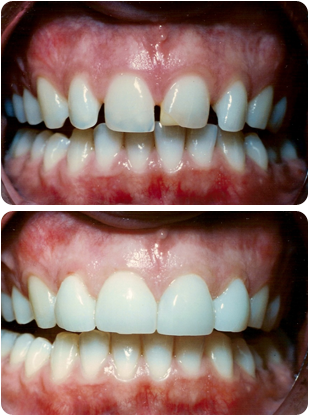

This is one of the picture where gaps has been closed by laminates.. This can be done in a weeks time ..If your concern is somewhat related to this condition , you can come to our clinic for free consultation, and we can discuss about different treatment options.

How to close gaps between the teeth?

Gaps between the teeth can be closed by either pulling the teeth together with braces orthodontically or cosmetically by placing porcelain laminates, lumineers or metal free crowns. If only spacing is a problem then either of it is a good option; however if teeth are malformed or missing resulting in the presence of gaps then directly going in for cosmetic correction is a more viable option.

What is cosmetic treatment or Smile designing? It is an artistic method to align your teeth and beautify your smile. In this we design the crowns so as to close the gaps between the teeth. Laminates and Lumineers are relatively non invasive methods of achieving gap closure along with change in colour and shape of the teeth when the teeth are perfectly aligned.

What is the investment required in terms of time? Orthodontically correcting the teeth requires 7-8 months while cosmetic correction is achieved within 7-10 days.